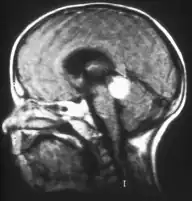

Aspect of trilateral retinoblastoma on MRI -